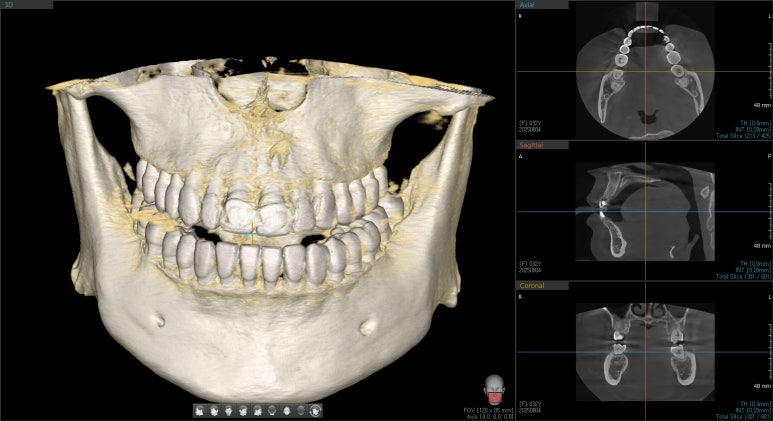

25.08.04 첫 내원

엑스레이 검사 결과, 뿌리 끝에는 염증도 생겨 있었습니다.

단순히 겉모습의 문제만이 아니라, 치아 뿌리 쪽도 치료가 필요했던 상황이었습니다.